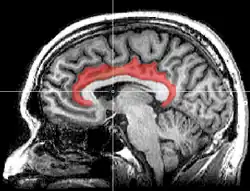

Střední povrch mozkové hemisféry. Střední pohled. Hluboká pitva.